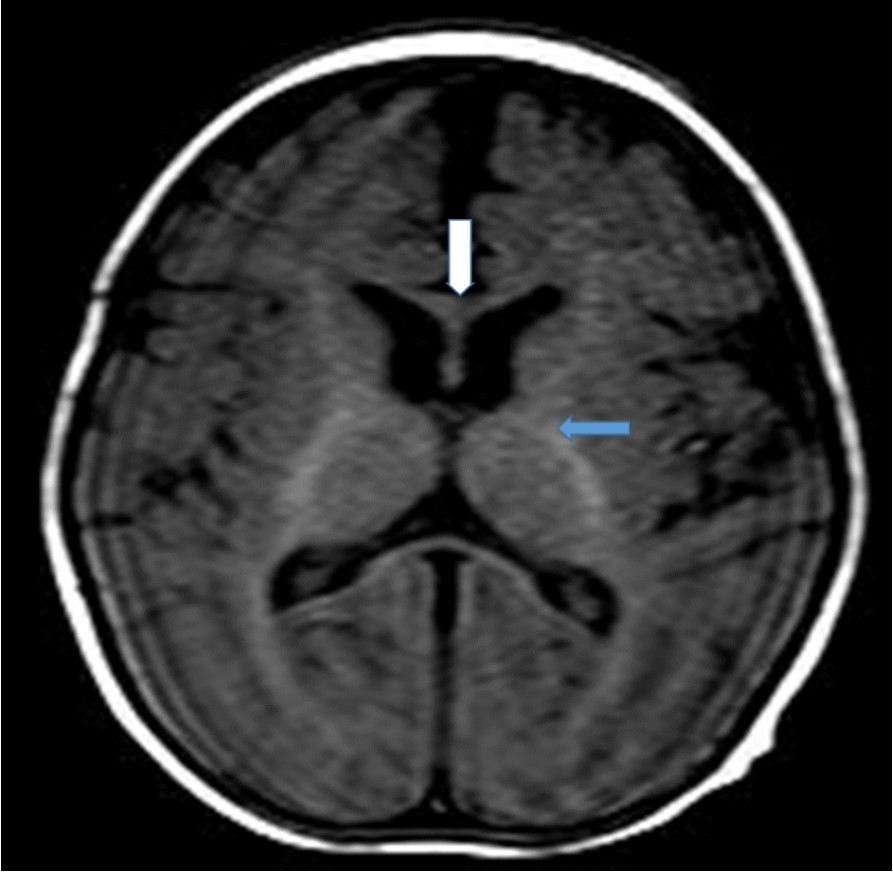

Cranial magnetic resonance imaging (MRI) was requested owing to the patient’s convulsion history and retarded development. The cranial MRI showed diffuse hypoplasia of the corpus callosum in the midline sagittal T2-weighted image (Figure 1 white arrow). T1-weighted imaging showed hypointensity due to delayed myelination of the genu of the corpus callosum (Figure 2, white arrow), which should normally appear hyperintense like the posterior limb of the internal capsule (Figure 2, blue arrow).

Figure 2.T1-weighted magnetic resonance image of the patient (7-month-old girl). The genu of the corpus callosum is hypointense due to myelination delay. In this age group, the genu of the corpus callosum should become hyperintense similar to the posterior limb of the internal capsule (blue arrow) due to myelination.

T1-weighted magnetic resonance image of the patient (7-month-old girl). The genu of the corpus callosum is hypointense due to myelination delay. In this age group, the genu of the corpus callosum should become hyperintense similar to the posterior limb of the internal capsule (blue arrow) due to myelination.